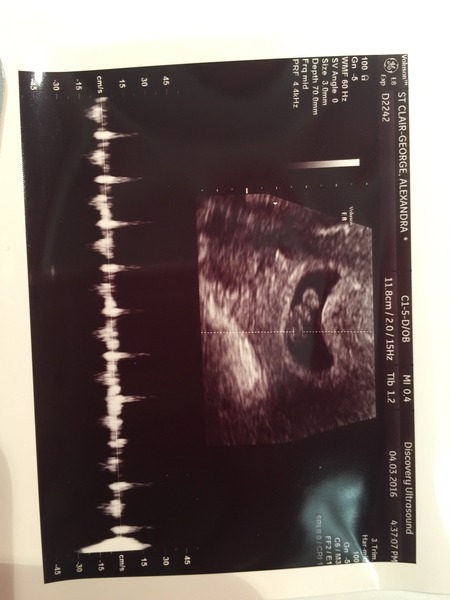

obsessedlex · 04/03/2016 18:01

Hi all thank you so much for your kind messages! Well I survived, and little bean has a lovely strong heartbeat which we saw and heard and is measuring 8w2d so I've actually gained a day!! Obviously I sobbed like a lunatic and still don't feel like I can breathe properly!

Not the best picture but thought I'd share - and that's the heartbeat at the bottom xxx